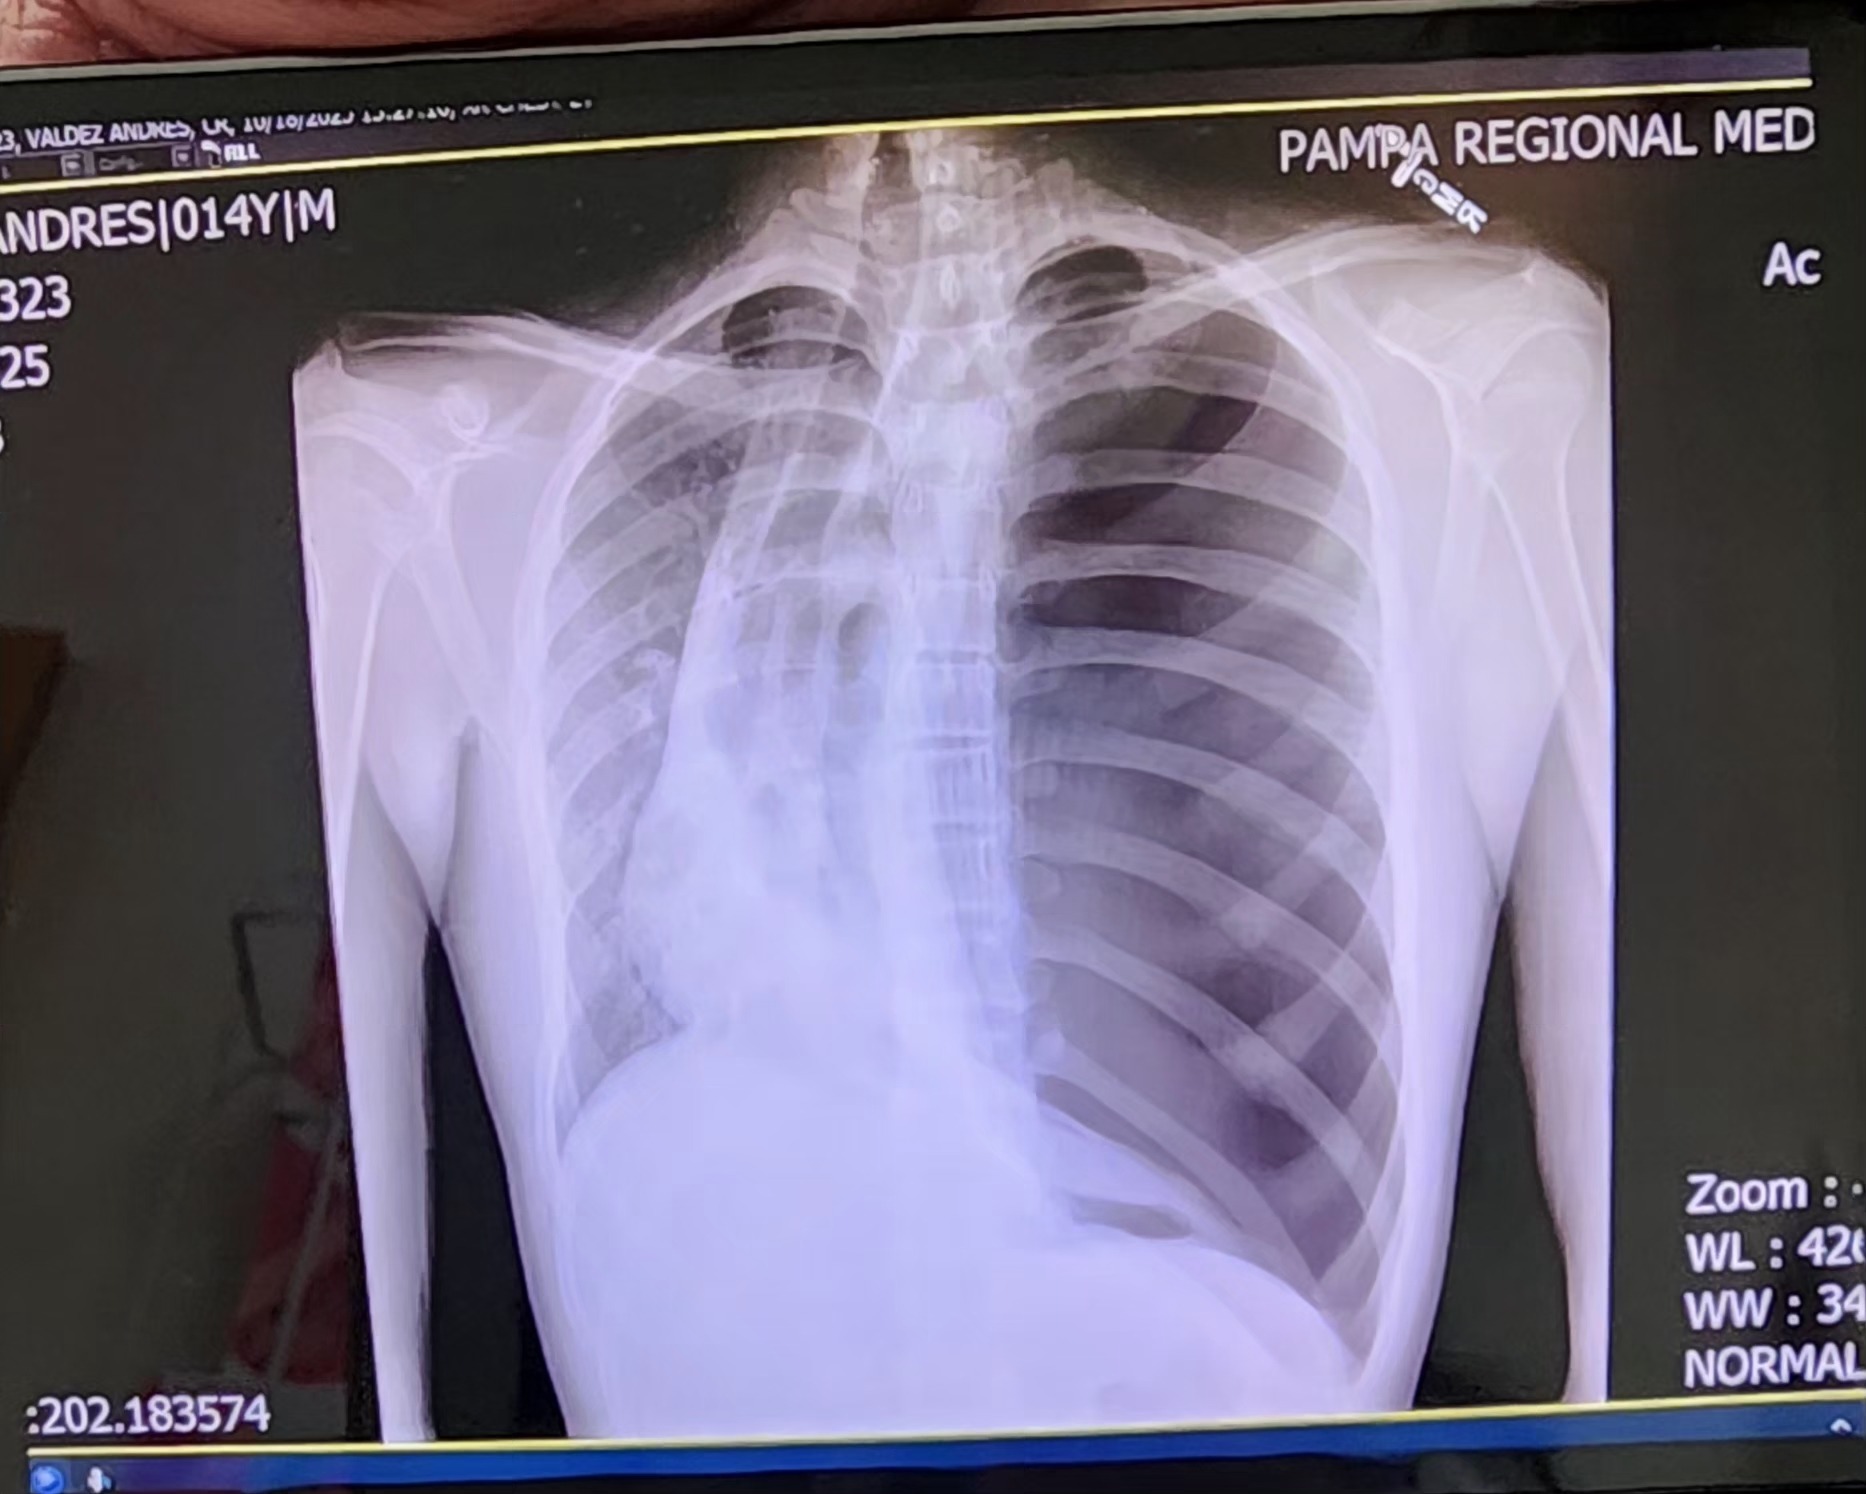

Hello, my name is Andy. I recently was hospitalized with a collapsed lung. I'm 14, a freshman at HISD. Anything will help with helping my family pay for any medical expenses not covered by insurance.

My doctor is planning a surgery to correct what's causing my lung to collapse this coming week. Thank you!